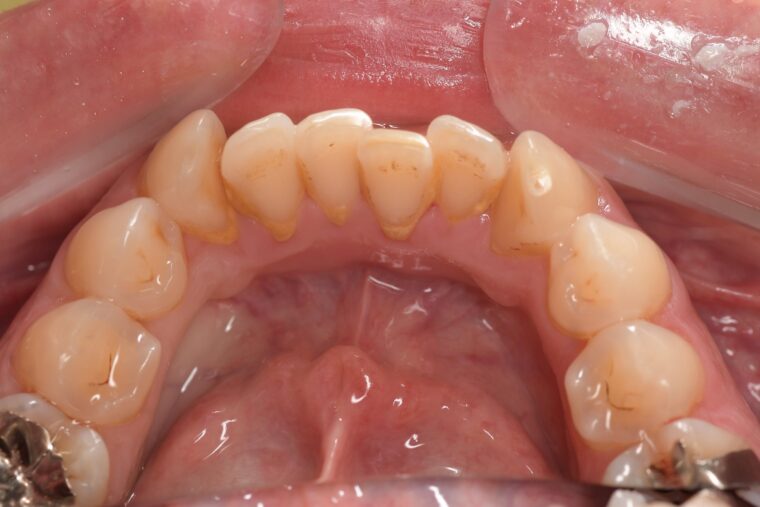

CASE 3

Before

After

基本情報

| 年齢・性別 | 30代・女性 |

| 主訴 | 定期検診 |

| 治療内容 | PMTC |

| 治療期間 | 60分 |

| 治療費 | 5,750円 |

| リスク・副作用 | しみる可能性があります。 |

| 治療方針 | PMTCでステインの除去。 |

| 担当者所見 | ステインが付きやすいため、3カ月毎の定期検診で除去する。 |